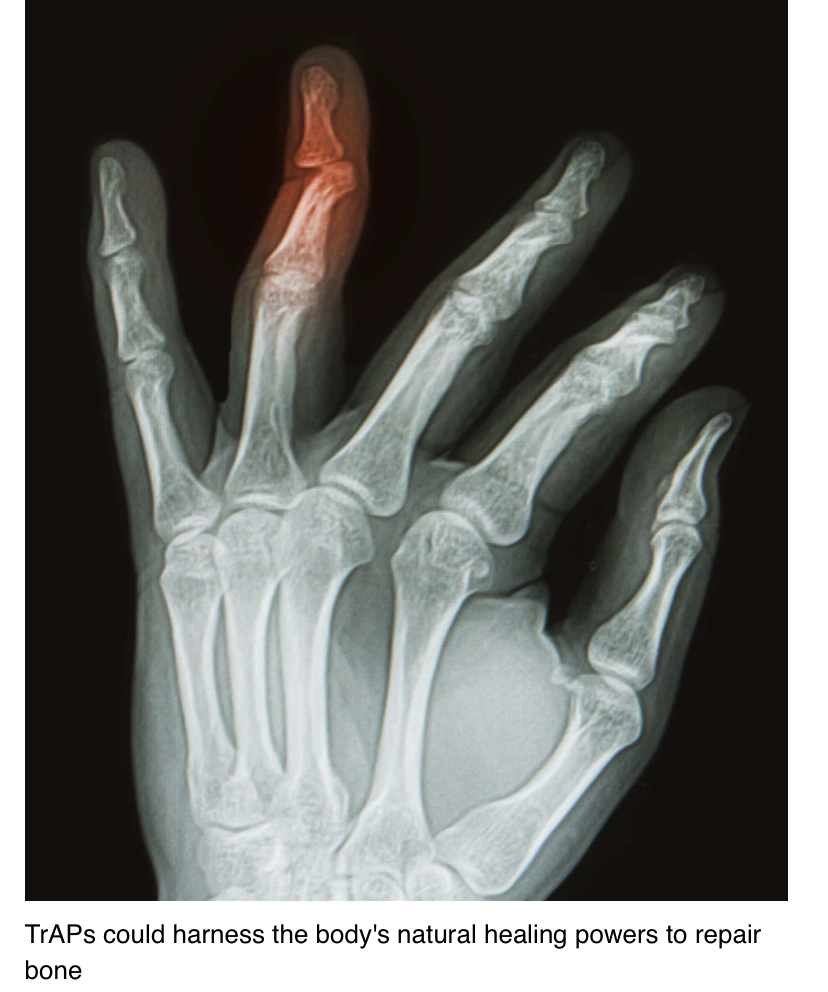

X-ray of hand with broken ring finger

TrAPs could harness the body’s natural healing powers to repair bone

يمكن لـتقنية TrAPs تسخير طرائق الشفاء الطبيعية  لإصلاح كسور العظام والمفاصيل والأصابع